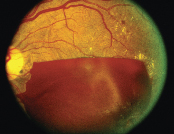

![]() 視網膜脫落 |

![]() 玻璃體出血 |